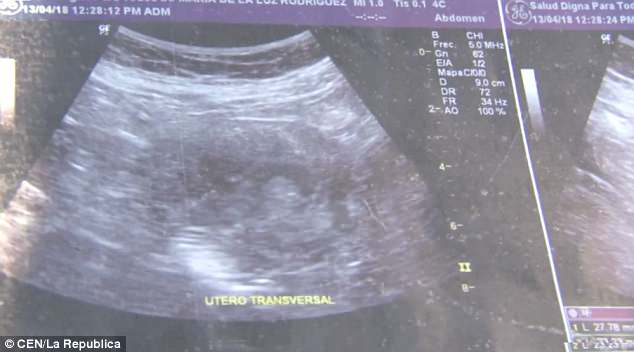

Η Μαρία Ντε Λα Λουζ έδειξε στους δημοσιογράφους υπερηχογραφήματα, τα οποία σύμφωνα με την ίδια επιβεβαιώνουν ότι είναι 6 μηνών έγκυος και περιμένει κοpιτσάκι.

“Μου είπαν ότι είναι κοpίτσι. Κοιτάξτε, μπορείτε να δείτε το πρόσωπό της”, ανέφερε η 70χρονη γυναίκα από το Μεξικό.

Ένα από τα υπερηχογραφήματα της Μαρία Ντε Λα Λουζ.